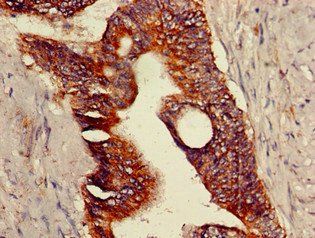

Immunohistochemical staining of human colon cancer using TRPV1 antibody